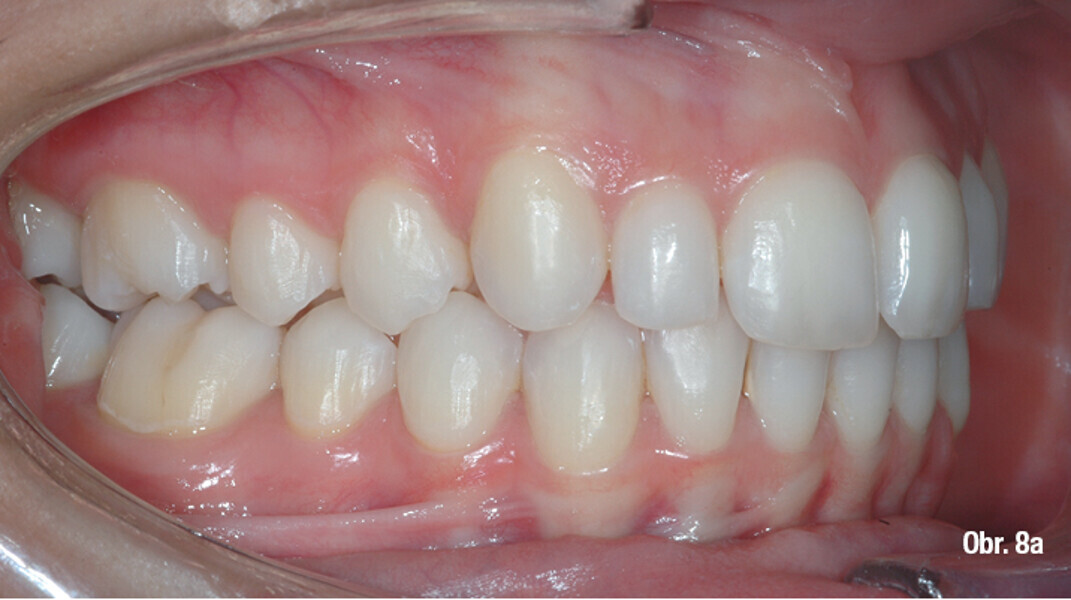

Distalizace horních molárů pomocí alignerů a cyklických sil